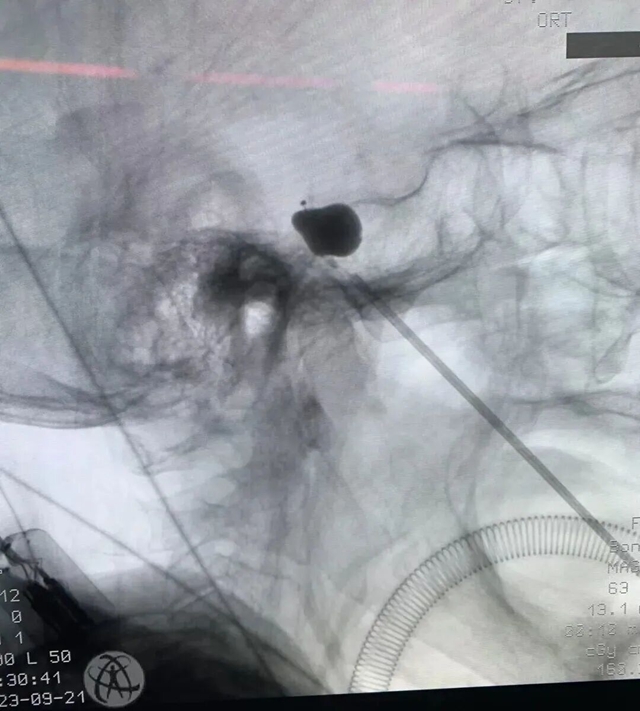

为积极响应及落实“健康中国2030”行动,推动医疗服务从疾病治疗向全生命周期健康管理转型,更好地向广大病友提供专业的健康...

2026年3月20日,农历二月初二,春分适逢龙抬头。在泸州市纳溪区上马中心卫生院的疼痛科诊室里,一位头痛患者送来锦旗,感...